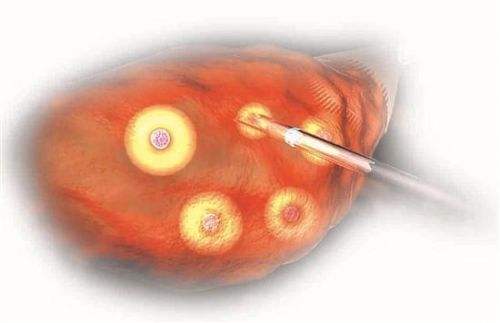

在门诊,患者经常会问:“医生,取卵手术到底痛还是不痛啊?为什么有的病友说没什么感觉、有些酸胀,有的病友说稍微有些痛、能忍受,还有病友却说非常痛、痛得死去活来……”...

试管婴儿过程是由一系列的步骤组成的,每一步都至关重要,取卵环节是医生完成的一个环节,很多患者对取卵很好奇,不知道试管婴儿所需要的卵子是如何从女性的体内取出来的。关...